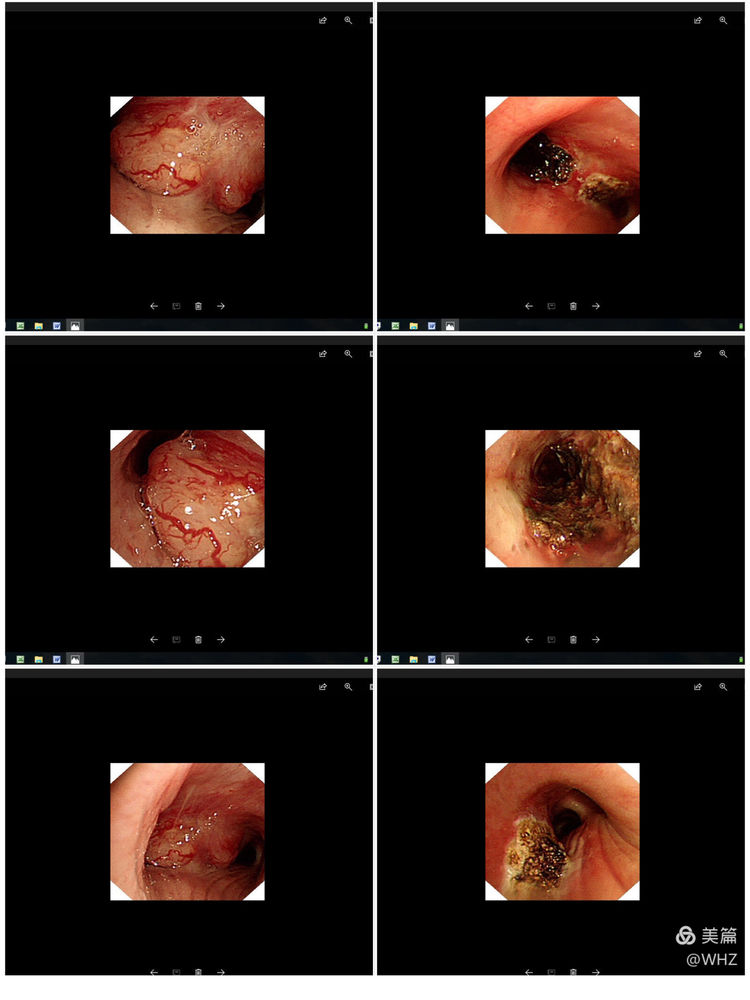

呼吸与危重症医学科和麻醉科经过认真的术前讨论和充分的准备,于8月2日为患者进行气管镜下APC(氩等离子体凝固)肿瘤切除术。术中发现左主支气管新生物浸润样生长,管腔不完全阻塞,仅剩15%左右,予以APC烧灼肿瘤后管腔增宽至80%,右主支开口处粘膜受累,管腔不完全阻塞,予以APC烧灼肿瘤组织。手术顺利,术后患者胸闷、喘憋明显减轻,吸气相哮鸣音消失。目前已顺利出院。

治疗前与治疗后比较